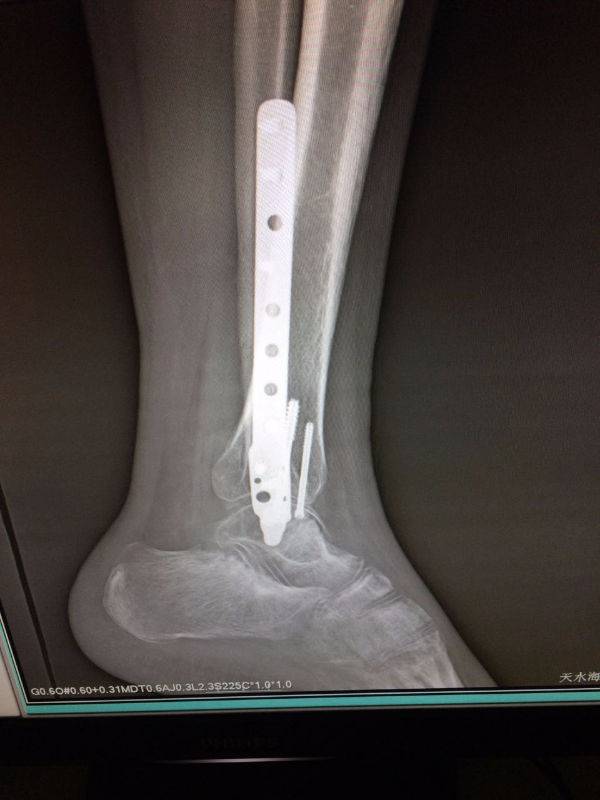

手术非常好,顺便请教一下。患者.男,25岁,右腓骨下段及内踝骨折,切开复位内固定术后120天,外踝部钢板外露,半月前行扩创缝合,目前仍未完全愈合,伴少量渗出,踝关节功能僵硬。请教治疗方案。谢谢

mmexport1496478334909.jpg